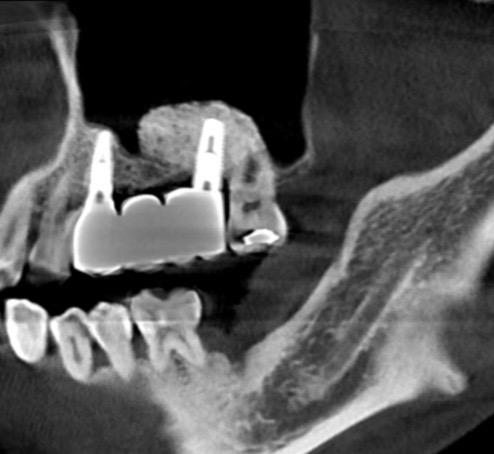

下記の症例は上顎臼歯部(上の奥歯)の骨量が不足している症例に対し、難易度の高いサイナスリフトを行い、骨量を改善させたのちインプラント埋入を行いました。

このような治療方法は特別なトレーニングを継続して受けなければ身につきません。